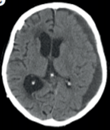

Chronic subdural haematoma ( #CSDH) is a common neurological condition in elderly individuals, and its incidence is rising due to an ageing population and increasing use of anticoagulant and antiplatelet medication.

Inflammation plays a central role in the pathogenesis of #CSDH. A good recent review by @EdlmannE can be found here https://pubmed.ncbi.nlm.nih.gov/28558815/ (open access)

The trial recruited 748 patients in just over 3 years and was published last week online @NEJM. The visual abstract (thanks to @BranGSmith) is below.

The results are interesting as although dexamethasone reduced post-op recurrence, it led to more unfavourable outcomes at 6 months (primary outcome measure). Hence, on this basis, we have recommended that the use of dexamethasone for #CSDH should STOP